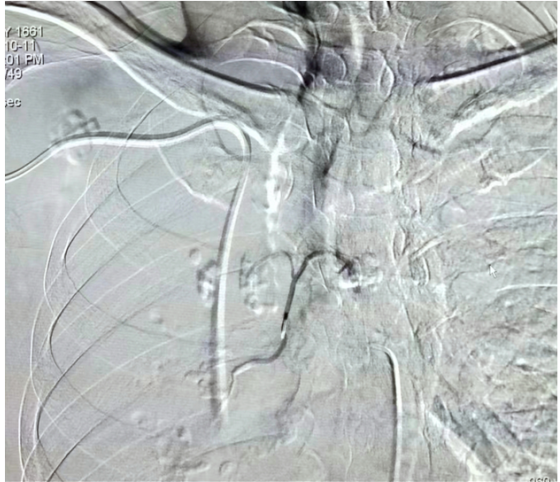

行支气管动脉造影见左、右侧支气管动脉共干、左侧支血管异常粗大,显影欠佳,左下肺隐约可见空洞影。

在进行支气管动脉超选择性栓塞后,可从影像中看到主要血管均有栓塞剂沉积影,未见造影剂,栓塞效果良好。